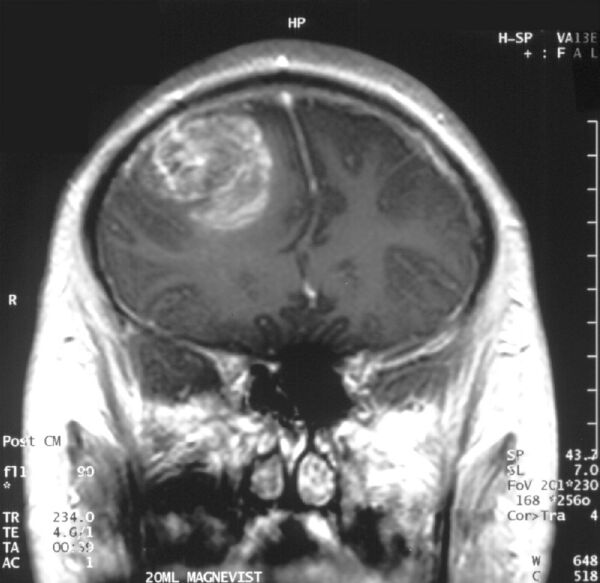

Контрастное МРТ-сканирование при глиобластоме у 15-летнего мальчика

Сагиттальное контрастное МРТ-сканирование при глиобластоме у 15-летнего мальчика